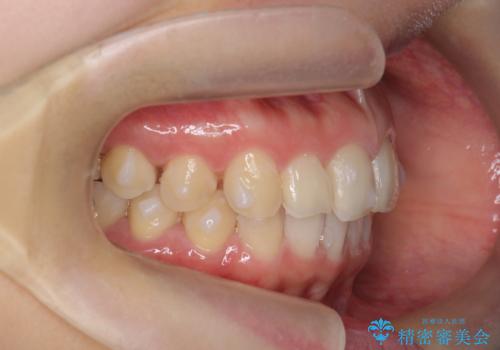

出っ歯に見える前歯の改善 部分ワイヤーとマウスピース矯正

- 出っ歯に見える前歯の改善を希望され、来院されました。

マウスピースでは改善の難しい歯の動きを部分ワイヤー矯正で整えたのち、奥歯の噛み合わせや細かい歯の並びをマウスピース矯正インビザラインで整えていきます。

最終的な前歯の並びに大変満足いただくことができました。